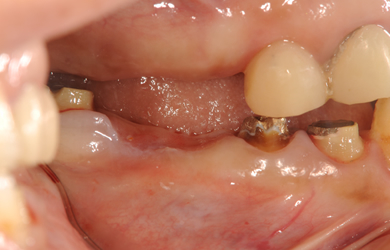

治療前

• 治療前

主訴 ブリッジが外れ、セラミックが割れて見た目が気になります。一年前に他の歯科医院に相談に行きましたが、インプラント治療は難しいと言われました。もともとその部分はインプラントでの治療を希望していたので、この機会に治したい。

治療方針 右上の骨がほとんど無いため、サイナスリフト法に再生療法を組み合わせ上顎洞底部を挙上することにより、骨の無い部分に骨をつくってあげ、インプラント治療を可能にする。

治療内容 インプラント5本(抜歯即日スピードインプラント+サイナスリフト+GBR+クラウンレングスニング)、ハイブリッドセラミック8本